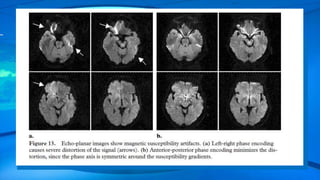

Echo-planar images generally are subject to more severe susceptibility artifacts because

the echoes are refocused by using gradient refocusing over a long period.

One way to minimize this distortion is to orient the phase encoding gradient along the

same axis as the susceptibility gradients.

Susceptibility Effects : Theeffect of tissue magnetization slightly alters the local magnetic field. The difference in tissue susceptibility causes field inhomogeneity between tissue boundaries, which makes spins dephase faster, producing signals of low intensity. This signal loss is especially severe at air-tissue or bone–soft tissue boundaries, because air and bone have much lower magnetic susceptibility than do most tissues . Local magnetic fields tend to take on different configurations around these interfaces, and the difference introduces geometric distortion into the resultant images, especially when sequences with long echo times are used. SE sequences are less affected by local field inhomogeneity because of the 180° refocusing pulse, which cancels the susceptibility gradients.

Echo-planar images generallyare subject to more severe susceptibility artifacts because the echoes are refocused by using gradient refocusing over a long period.

One way tominimize this distortion is to orient the phase encoding gradient along the same axis as the susceptibility gradients. The best way to minimize susceptibility artifacts is to use an SE sequence or reduce the echo time ,increase the acquisition matrix , and improve shimming . metal-related artifacts typically are manifested as areas of complete signal loss because the local magnetic field is so strong that the spins are almost immediately dephased. Sometimes, depending on the strength of the resultant distortion of the magnetic field, part of a section may appear on images acquired in a completely different section because of the frequency difference between the spins in the metal and those next to the metal.